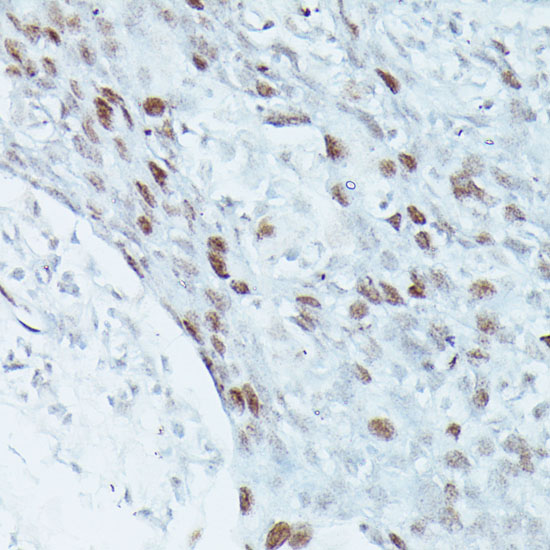

Immunohistochemistry of paraffin-embedded rat brain using MEF2C antibody at dilution of 1:100 .Perform microwave antigen retrieval with 10 mM PBS buffer pH 7.2 before commencing with IHC staining protocol.

Immunohistochemistry of paraffin-embedded human breast cancer using MEF2C antibody at dilution of 1:100 .Perform microwave antigen retrieval with 10 mM PBS buffer pH 7.2 before commencing with IHC staining protocol.